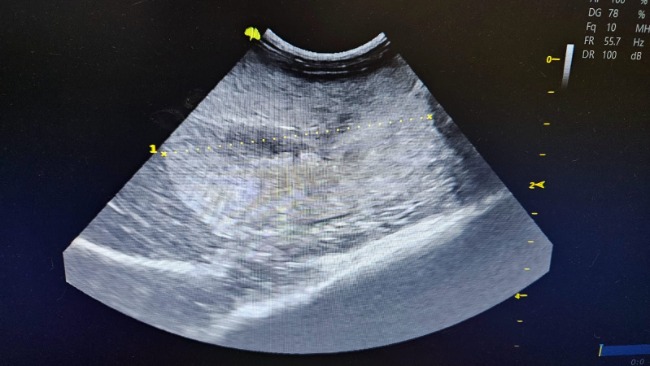

PNN czyli przewlekła niewydolność nerek.

Nieuleczalna. Nerki na usg w złym stanie.

Mocznik,kreatynina parametry bardzo przekroczone. Poza tym jest nieźle.